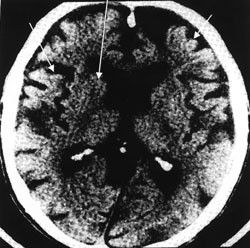

Ved Alzheimers sykdom ansees redusert perfusjon avgrenset til hjernens temporo-parietale regioner for å være en markør for Alzheimers sykdom og kan være uttrykk for substanssvinn i disse områdene (fig 3). I en nylig publisert studie, hvor man korrelerte cerebrale SPECT-forandringer hos pasienter med Alzheimers sykdom med senere autopsifunn, konkluderes det med at SPECT-undersøkelse er et nyttig hjelpemiddel ved klinisk mistanke om Alzheimers sykdom (23). Imidlertid setter andre forfattere spørsmålstegn ved SPECT-metodens presisjon og gyldighet i diagnostikken ved denne problemstillingen (24). Gjentatte undersøkelser over tid ved usikre kliniske symptomer kan gi diagnostisk tilleggsinformasjon, men også her mangler forskningsdokumentasjon. Metoden anbefales imidlertid brukt på spesialistnivå som et supplement til cerebral CT eller MR ved mistanke om patologiske forhold frontalt (25). SPECT-metoden ser ut til å være spesielt velegnet for å påvise patologi i frontallappene i tidlig fase (26) (fig 4). Hypometabolisme begrenset til subkortikale strukturer, som man kan se ved subkortikal demens, kan imidlertid være vanskelig å påvise ved denne metoden. Ifølge den amerikanske konsensusrapporten (18) gir ikke SPECT-undersøkelser tilleggsinformasjon av betydning i forhold til dagens kliniske diagnostiske kriterier for demens, og metoden anbefales derfor ikke brukt rutinemessig.